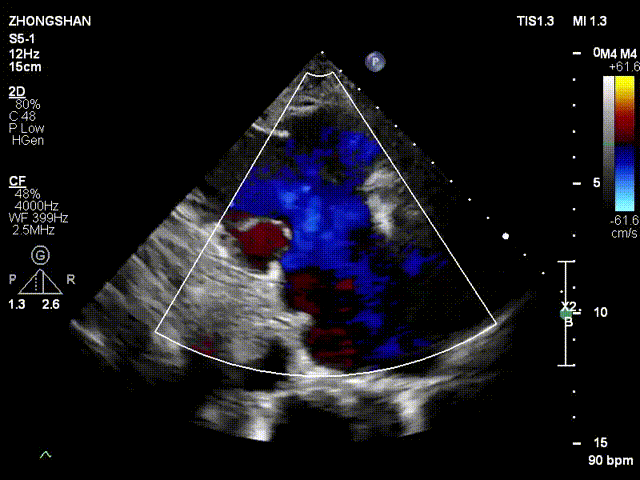

术前超声

术后超声